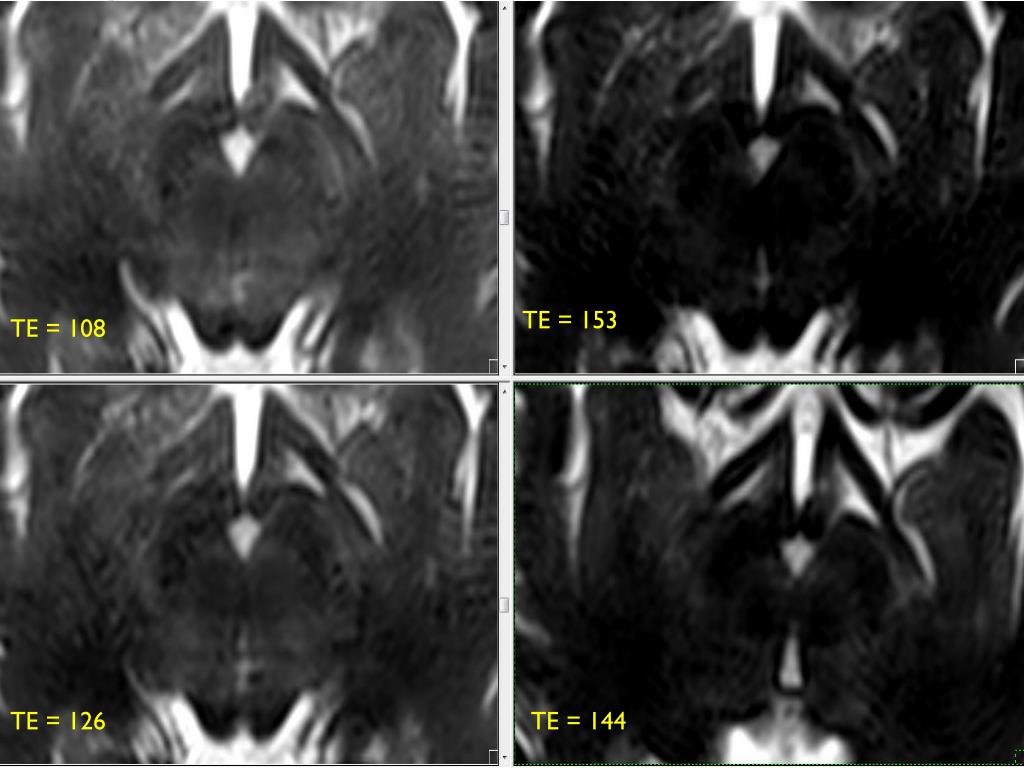

9. TE = 153 TE = 108 TE = 126 TE = 144